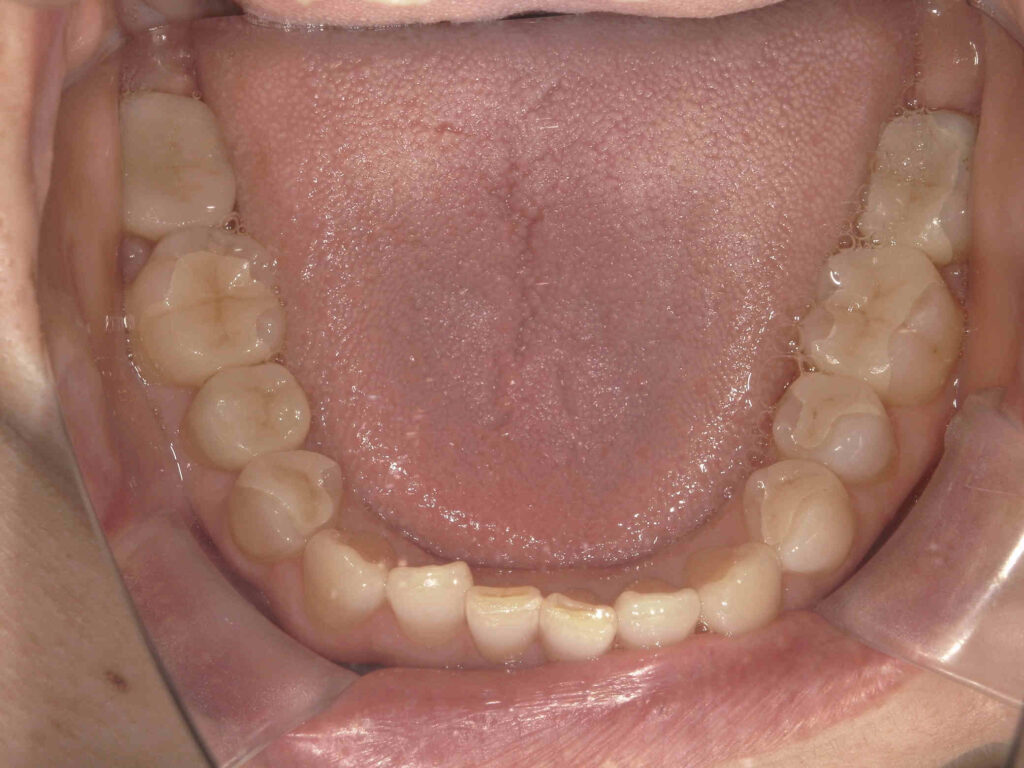

AFTER

銀歯が目立ちます

| 主訴 | 銀歯をなくしたい |

|---|---|

| 診断名・ 主な症状 |

メタルインレーによる審美障害 |

| 年齢 | 50代女性 |

| 治療内容 | グラデーションジルコニアインレー修復 |

| 治療期間/ 通院回数 |

2カ月/4回 |

| 費用 | 616,000円 |